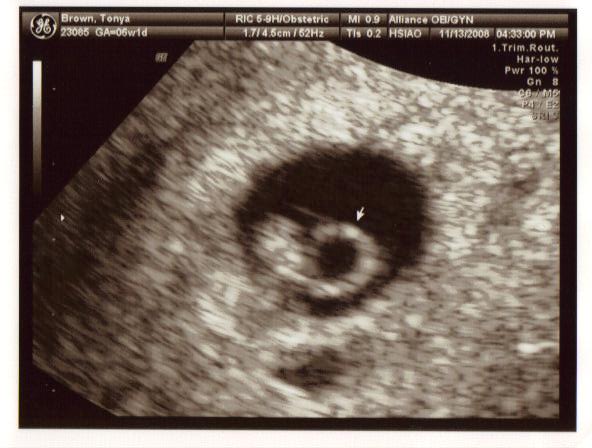

November 13, 2008

This was the biggest day in our lives so far, we were going to hear our baby(ies)’s heart beat for the very first time. Poor Tanya, she has been up all night sick and coming to the appointment, when she would rather just stay in bed, was miserable for her. I felt so sorry for her. Jeremy and I couldn’t contain ourselves, we were so anxious to find out how many babies we are expecting and hoping for that sign of life – healthy heart beat.

And there it was, faint but healthy and right on target – one baby, one heart beat! It was an amazing feeling. We saw and heard our baby for the very first time.

Tanya had some blood in her uterus, visible on the ultrasound but the doctor didn’t seem to be concerned about it, he said that it happens. She just needs to take it easy and it will disappear.

We were given a due date of July 8, 2009.

Our embryo is officially a PEANUT.

Here the arrow is pointing at PEANUT and its heart beat.

Here the arrow is pointing at the yolk sac that PEANUT is living off of.